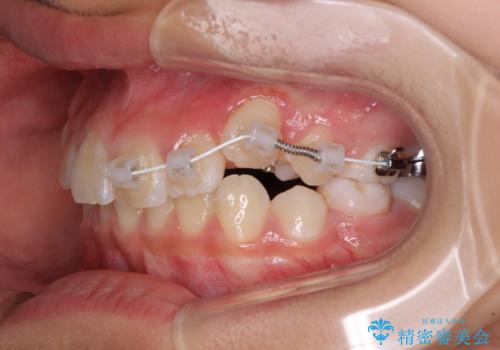

- 小学校での定期歯科検診にて歯列不正を指摘されたとのことで来院された患者様です。

左上の犬歯が低位に埋伏しており、将来八重歯になるリスクが高いと判断されたため、補助装置とワイヤーを用いて犬歯を通常の位置まで移動させることとしました。